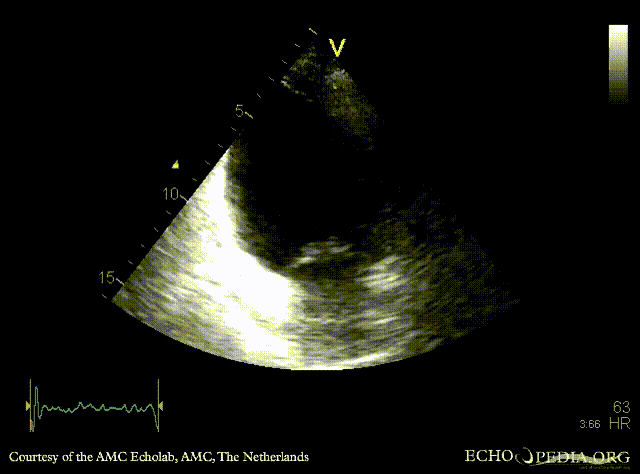

Infarction of posterior and inferior wall

Courtesy of: AMC Echolab, AMC, The Netherlands

E00524.gif E00525.gif

PLAX: dilated left ventricle, akinesia of posterior wall PSAX: akinesia of posterior and inferior wall